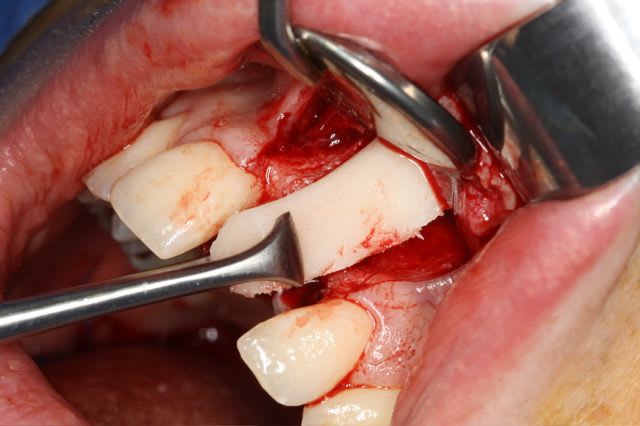

dépose des vis et pose de l'implant à 5mois1/2 avec un cj roulé et mise en place de la vis de cica,

Non pas speedy mais straight: apex moins agressif et implant moins compressif

J'ai eu beaucoup de craterisation avec le speedy ( surtout sur des sites anciens ) et sur une greffe je préfère la mise en place plus douce du straight pour ne pas risquer de 'décoller' le greffon cortical